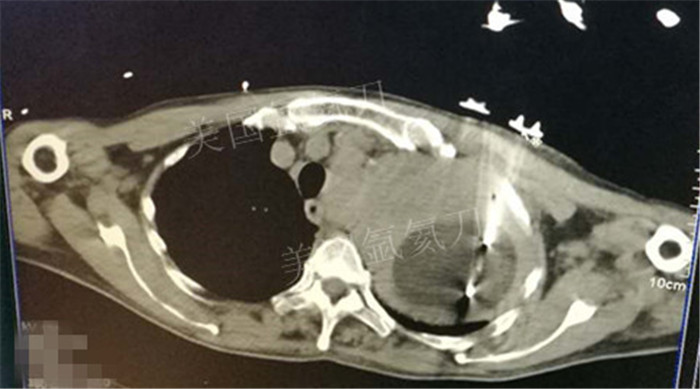

上一篇:煤炭总医院氩氦刀冷冻消融治疗双肺转移病灶